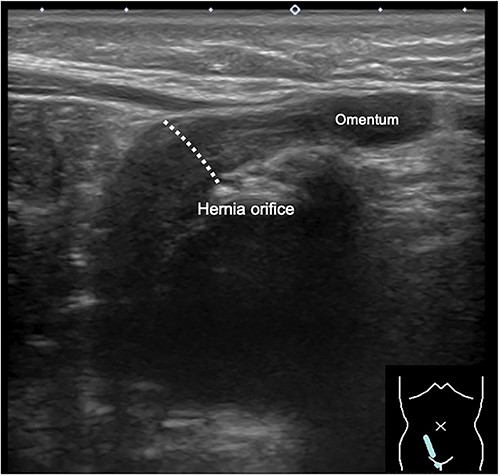

When the patient turned 1 year old, a laparoscopic percutaneous extraperitoneal closure (LPEC) procedure was carried out to address the bilateral inguinal hernias. Although the uterus was slightly deviated toward the right side of the pelvis, its position appeared to make it difficult for the uterus to herniate through the hernia orifice. The right fallopian tube was located near the hernia orifice, and a high ligation was carefully performed to avoid entanglement of the fallopian tube (Fig. 3). The procedure was concluded successfully without any significant complications. Subsequent follow-up examinations conducted after one year showed no recurrence of the inguinal hernia.

Findings during laparoscopic inguinal hernia repair (Laparoscopic Percutaneous Extraperitoneal Closure: LPEC) conducted at the age of 1 year. (A). Preoperative observations: The patent right inguinal hernia orifice was confirmed. The uterus and fallopian tubes were located close to the hernia orifice, but there was no evident protrusion, and the uterus was not in a position to prolapse. (B). Postoperative observations: High ligation was safely performed, with special attention given to the fallopian tubes.